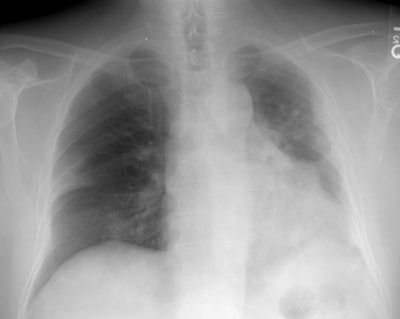

The patient below had received radiation therapy to the left chest for an axillary liposarcoma 6 months previously. The patient presented with complaints of increasing shortness of breath and a dry cough.

Initial CXR revealed patchy right lung infiltrates. Post radiation fibrosis is noted along the left lateral hemithorax. (Click image to enlarge)